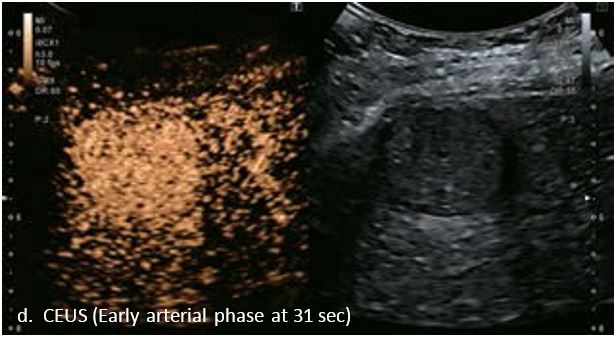

LI-RADS 5 ГЦК

У 63-річної жінки з алкогольним цирозом печінки виявлено ураження печінки розміром 3 см. Межа ізоехогенного ураження та його гіпоехогенний ореол може бути чітко відображений на сірошкальному зображенні. За допомогою кольорового доплера можна виявити внутрішньопухлинну судинну структуру. Багата судинна структура може бути окреслена за допомогою SMI, та можуть бути показані викривлені судини, що свідчить про злоякісне ураження. Після ін'єкції контрасту, в артеріальній фазі, ураження демонструє гомогенне гіперпосилення, пов'язане з підживлюючими судинами. Вимивання не спостерігається на 1 хвилині і на 2 хвилині. У відстроченій фазі на 3,5 хвилині можна спостерігати помірне вимивання. Вимивання повільно прогресує і стає більш чітким на 5 хвилині. Пізнє (≥ 60 сек) і помірне вимивання є однією з основних ознак LI-RADS 5 і є дуже важливим для диференціації від LI-RADS M, який показує раннє (<60 сек) і/або виражене вимивання. В результаті ураження класифікується як CEUS LI-RADS 5. Класифікація CEUS LI-RADS відповідає LI-RADS на КТ.

Малюнок 9